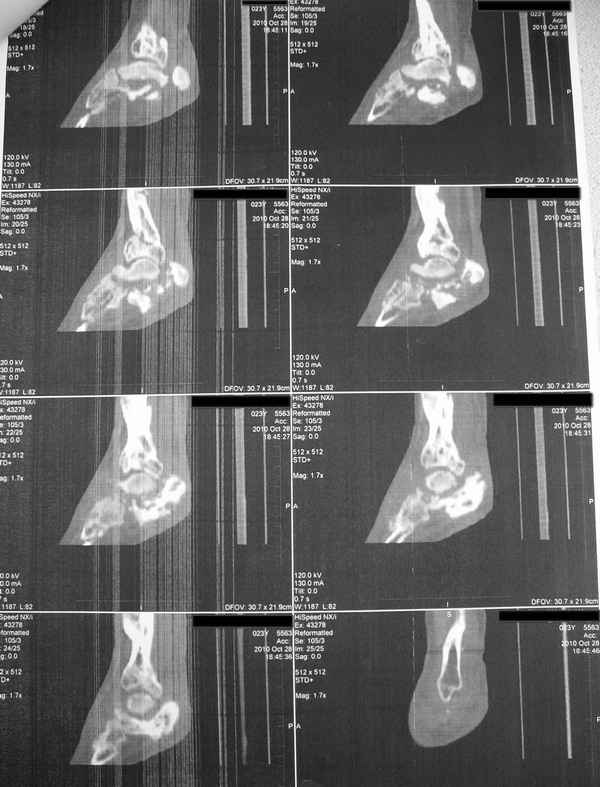

Молодая девушка со сросшимися многооскольчатыми переломами пяток и голеней.Young girl with fractures of the calcaneus Больная Н., 25 лет, падение с высоты (2008 г.). Жалобы на боли в области голеностопных суставах, в области пяток при ходьбе. Лечилась в аппаратах внешней фиксации по поводу открытых оскольчатых переломов обеих голеней, переломов пяток. Далее по поводу несросшихся переломов голеней –ЧКОС аппаратами внешней фиксации. Переломы срослись, аппараты демонтированы весной 2010г. В левой пяточной области в месте проведения спицы имеется сукровичное отделяемое. При ревизии гноя нет. Чем помочь девушке?

Patient N., age 25, falls from heights (2008). Complaints of pain in the ankles, in the heel when walking. She was treated by external fixation on open comminuted fractures of both legs, fractures of the calcaneus. Then she was treated by external fixation from nonunion of both legs. Now fractures are fused, apparatuses removed in the spring of 2010. How to help a girl?

Добрый вечер!Посев на флору и чув-ть к ан-м из отделяемого левой пяточной кости.После результатов ответа.Трехсуставной артродез с костной пластикой, (трансплантат из крыла подвздошной кости в подтаранный сустав) низведение пяточной кости винт-стержень в пяточный бугор, АВФ спице-стержневого типа, обязательная фиксация и тракция стопы. Условие, позволяют мягкие ткани в правой пяточной кости выполнить операцию.При таких взрывных переломах,первоначально необходимо проводить стержень в пяточную кость,удобно репонировать низводить,проще в дальнейшем выполнить артродез.Успехов!